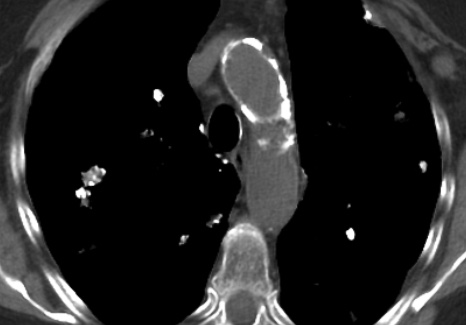

Amyloïdose Pulmonaire Nodulaire

- Dépots de Nodules (Amyloïdomes) Souvent calcifiés

- Peuvent avoir des kystes

- Souvent confondu avec des métastases (dans le DD), en plus ils captent le FDG !